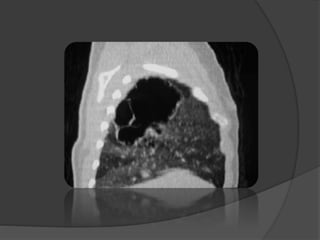

LE SCANNER THORACIQUE

 Masse kystique ou tissulaire

 Anomalies de perfusion en périphérie

 TDM+ PDC ====> EXAMEN DE CHOIX

artère systémique + étude du retour

Artère naissant du bord

latéral gauche de l’aorte

destinée au LIG

Masse kystique du LIG

avec hypovascularisation

localisée